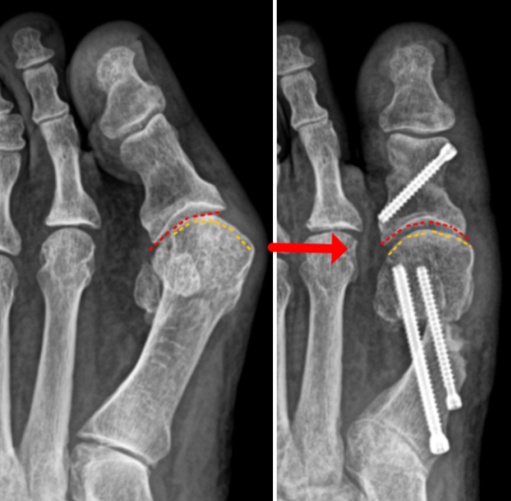

발뼈 튀어나옴 무지외반증 증상 안녕하세요 하니하둥입니다. 요즘 저도 발뼈가 튀어나오며 무지외반증에 대...